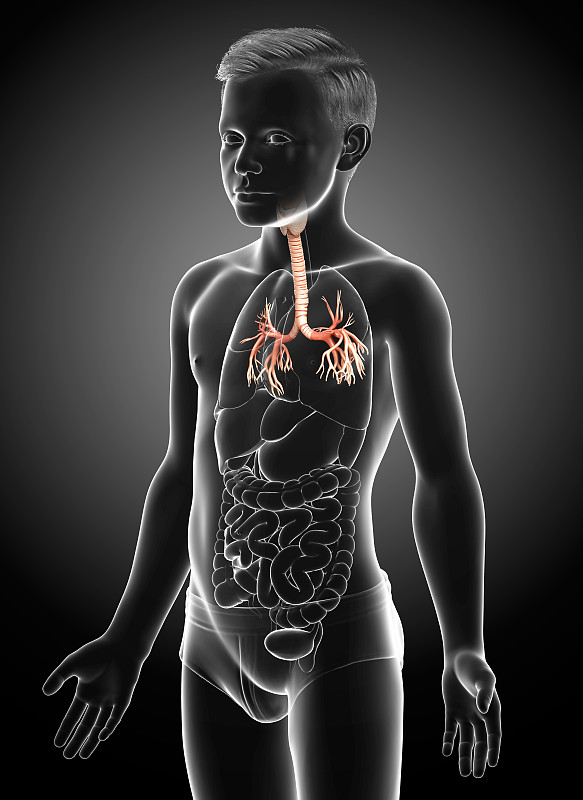

人体呼吸系统肺解剖详情

JPG

人体呼吸系统肺解剖详情

JPG

人体呼吸系统肺解剖学详情

JPG